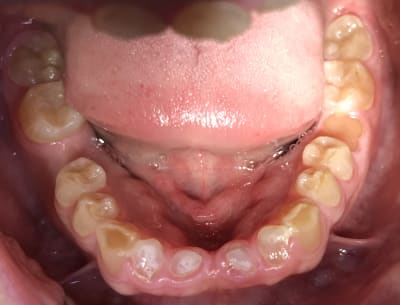

Photos

9db1a8f8 0abe 44f7 87a9 75959bc99136 uojbwk - Eugenol

E2f69a8e 1293 4d24 bc42 b326036451b8 xx21g7 - Eugenol

40edc7b8 ac35 4fb0 a890 d3676a6f086c zc7npz - Eugenol

F210636b b920 48ee 9616 3728267b0311 w3y9lx - Eugenol

poignée de porte a diagnostiqué une maladie genetique, c'est un cas d'amélogenèse imparfaite avec racines courtes, obliteration des chambres pulpaires, émail fin et de mauvaise minéralité pour du collage... necrose en lien avec l'usure (les incisives inf)

Oui Mla2 problème génétique + bruxisme. Quand vous expliquiez qu’il était camé moi je veux bien mais bon regardez ses 6 . Ses prémolaires sont quasi intacts . Ils se seraient foutus de l’acide juste sur ses incisives et ses molaires .... étrange. :)

L'amélogénese imparfaite, toutes les dents sont touchées à égalité; et l'émail a un aspect visuellement altéré.